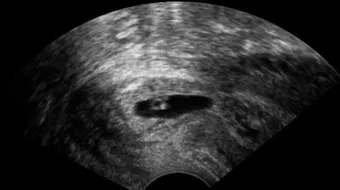

يجوز إسقاط الجنين المشوّه خلقياً قبل نفخ الروح فيه؛ أي قبل مرور مئةٍ وعشرين يوماً على الحمل، وذلك مشروطٌ بثبوت التشوّه بصورةٍ يقينيةٍ قاطعةٍ لا شك فيها، بقرارٍ من لجنةٍ طبيةٍ موثوقةٍ، وإن ثبت أنّ التشوه لا يمكن علاجه ضمن الإمكانات المتاحة، وذلك بالنظر إلى ما قد يسبّبه من المشّقات والصعوبات والحرج، إضافةً إلى التكاليف والمسؤوليات المتعلّقة برعايته والاعتناء به، إمّا إن بلغ الحمل مئةً وعشرين يوماً، ونُفخت فيه الروح؛ فلا يجوز إسقاطه بأي حالٍ، حيث إنّه أصبح نفساً بنفخ الروح فيه، لا بدّ من صيانتها والمحافظة عليها، سواءً كانت سليمةً أو مشوهةً، ويستثنى من ذلك ثبوت الخطر على حياة الأم، إذ يجوز إسقاط الجنين بعد نفخ الروح فيه إن ثبت أنّه يشكّل خطراً على حياة الأم، ويؤدي إلى موتها، وذلك بقرار لجنةٍ طبيةٍ موثوقةٍ، من باب ارتكاب أدنى الخطرين، وتحقيق أعلى المصلحتين.[1][2]